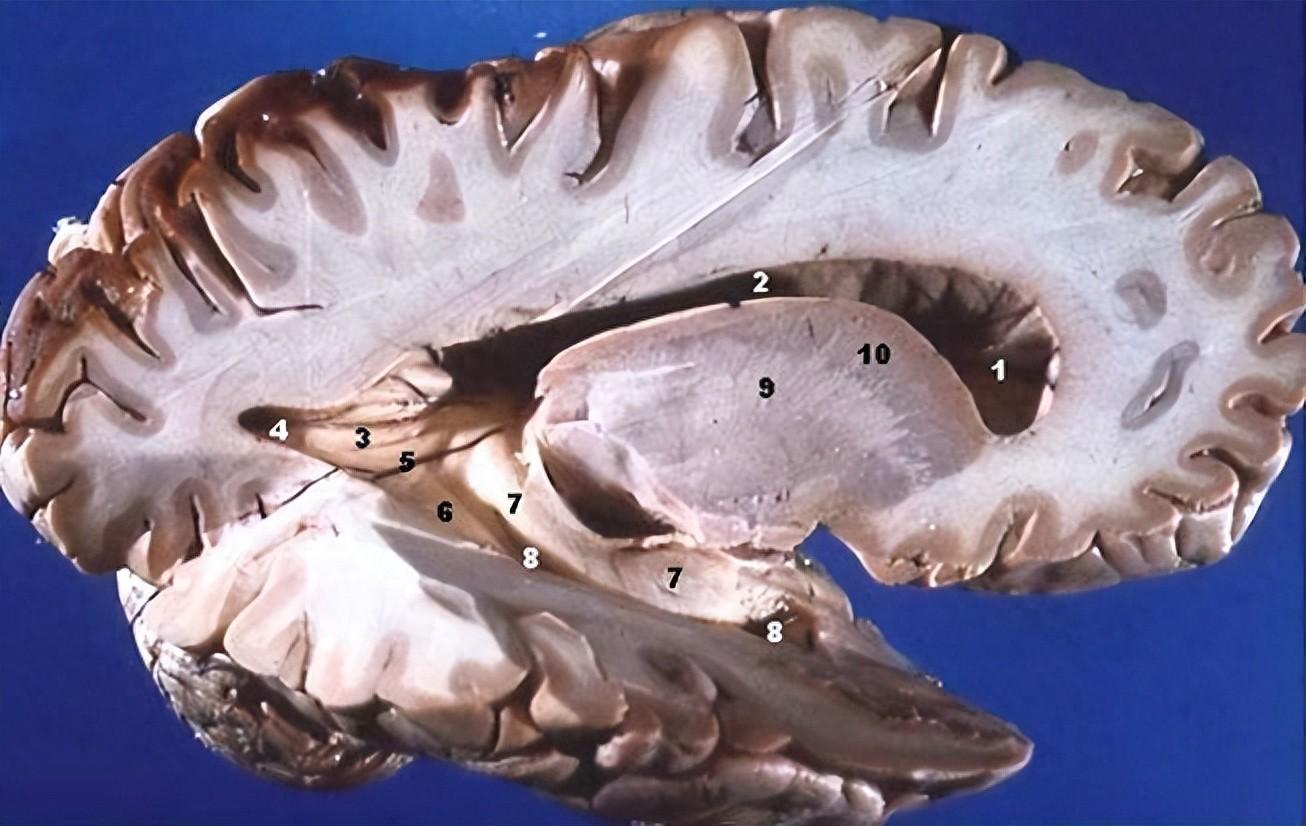

人腦的右側剖面圖

可看到灰質(外緣深色處,即大腦皮層)和 白質 (內部顯著偏白色的部分)

(圖片來源:維基百科)